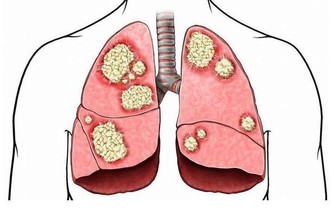

3.每天曬15分鐘太陽

適量多曬太陽能幫助人體製造維生素D,而研究表明維生素D有抗癌作用。